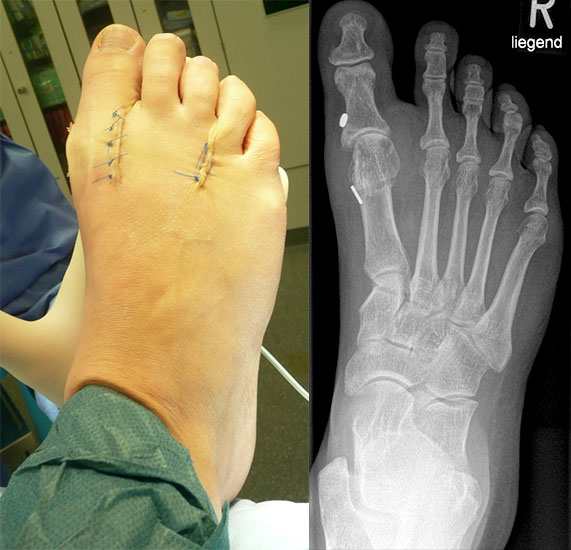

Arthrodese MTP I und weichteilige Rezentrierung MTP II und III (eigenes Bildmaterial)

Abbildung 18